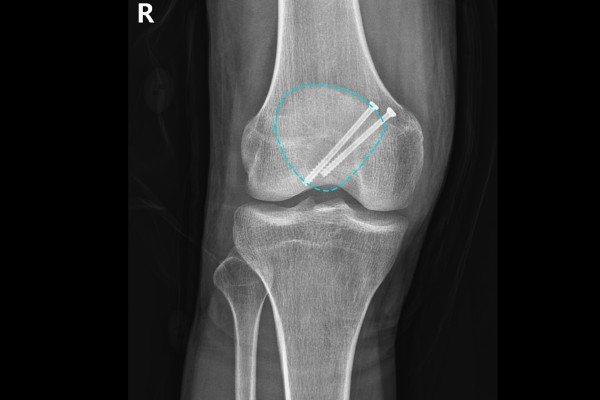

환자분께 X-RAY와 MRI를 보여드리며 상태를 설명드리고 수술을 진행하기로 하였습니다. 수술은 긴절개를 하지 않는 우측 슬개골 최소침습 골절고정술(Minimally invasive ORIF c screw)로 진행하였습니다.

9f695db682e5f1ea0b431dfdec73e7ff_1766564263_5761.jpg

수술 후 X-RAY를 보면 스크류가 슬개골 끝까지 부러진 부분을 잘 잡아주고 있는 것이 확인됩니다.

9f695db682e5f1ea0b431dfdec73e7ff_1766564272_5118.jpg

측면에서 봐도 골절선을 가로질러 잘 고정되어 있습니다.